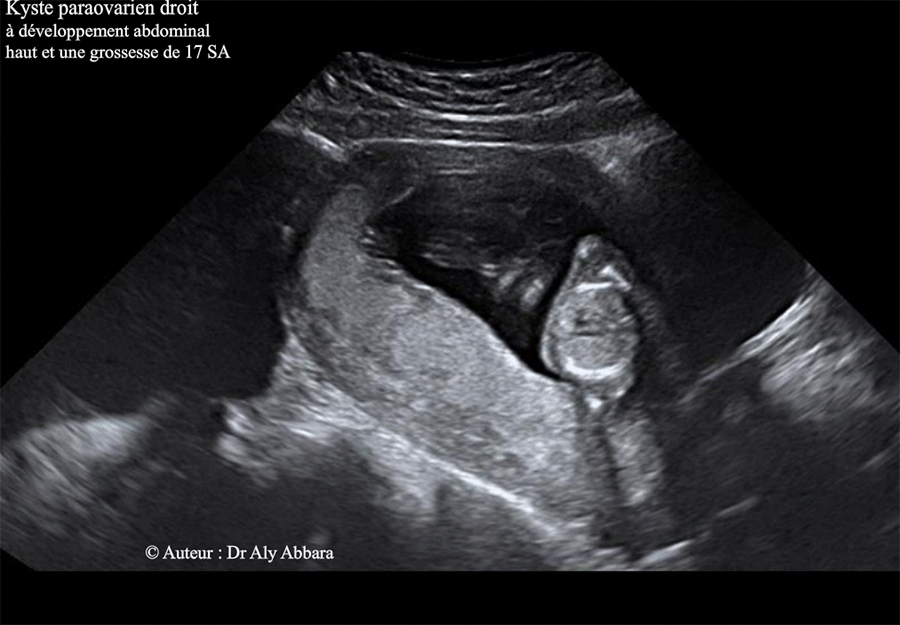

Kyste para-ovarien chez une femme enceinte de 17 SA - Images échographiques

Il s'agit d'un kyste uniloculaire de 200 x 110 x 106 mm de dimensions (soit environ 1230 cm3 de volume), à paroi fine, sans végétations endophytiques et sans épanchement péritonéal.